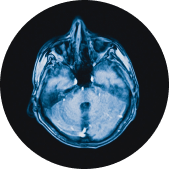

A traumatic brain injury is any damage to the brain or alteration of brain function caused by some external force, such as a car accident or slip-and-fall. A traumatic brain injury can be closed (meaning nothing penetrates the skull to damage the brain) or open (meaning something has broken through the skull to damage the brain).

A stroke occurs when something causes a disruption in the supply of blood to the brain. Strokes can be caused either by a clot that blocks blood flow or by a broken blood vessel causing blood to leak into the brain.

Brain aneurysms happen when an artery or blood vessel wall weakens, causing it to swell and form a blister-like shape. As the aneurysm grows, it can put pressure on the surrounding tissues and cause a range of harmful effects. If the aneurysm bursts, it can lead to a stroke.

A tumor is an abnormal mass of tissue inside the skull caused by cells dividing uncontrollably. Most tumors are not the result of an accident, but they can cause severe brain damage, nonetheless.

A hematoma or hemorrhage injury is when blood vessels rupture inside the brain, causing blood to accumulate in brain tissue and empty spaces within the brain. A hematoma is generally caused by a blood clot somewhere in the brain, while a hemorrhage is usually the result of some kind of blow to the head.

An edema is brain swelling, putting pressure on brain tissues as they press up against the skull. Left untreated, this pressure can lead to brain tissue damage and other effects.